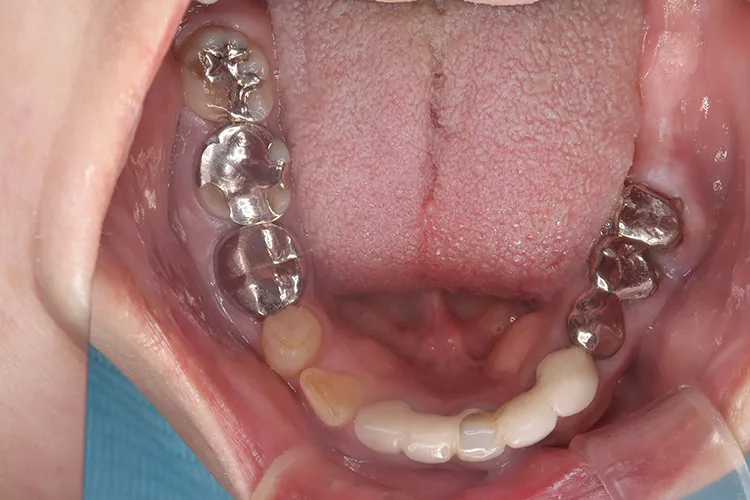

症例5/

前歯3本 臼歯2本

- 治療期間

- 10ヶ月

- 費用

- 177万円(税込)

治療前

治療後

レントゲン画像

治療内容

歯ぎしり・食いしばりが強い方の治療ケースです。全体的に歯が擦り減り正面から見て下の歯が見えないほど噛み合わせの高さが失われており、顎関節にも症状がでていました。ヒビが入って保存不可の歯を抜歯しインプラントを計5本埋入し、前歯・臼歯にインプラント土台のブリッジを入れることで噛み合わせの高さを回復しました。古い金属の被せ物もジルコニアでやりかえました。噛み合わせの高さが改善したことで顎関節症状もなくなり快適に過ごされています。歯ぎしりがある方は、夜間のナイトガード装着が必要になります。